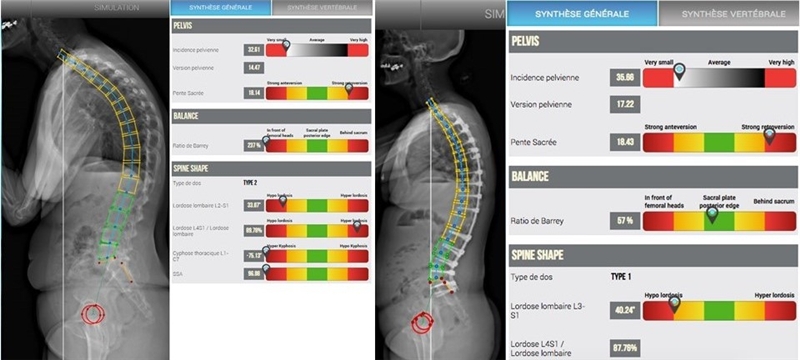

Roussouly教授于2005年建立了脊柱矢状位分型系统,被业界公认为脊柱矢状面研究方面的经典之作。Roussouly将正常人站立位腰骶部矢状面平衡归纳为四种形态:

1型:SS<35°,LL较小,前凸顶点位于L5中点,下腰弯角度很小趋于水平,呈现一条不协调的较长胸腰椎后凸和较短的腰椎前凸曲线,拐点偏低,位于L3。

2型:SS<35°,腰椎前凸顶点在L4,LL较小,下腰弯趋于水平,胸弯及腰弯均偏小,呈现协调的平背外观,拐点偏高,位于L1前方。

3型:SS值35~45°,LL前凸顶点在L4,平均有4个椎体参与腰椎前凸,LL的平衡性很好。呈现一条协调的几乎等长的胸椎后凸和腰椎前凸曲线,曲线拐点在胸腰段。是最常见的类型。

4型:SS>45°,PI也相对较大。LL前凸顶点在L3或更高位椎体,胸弯偏大,呈现一条协调的较长的腰椎前凸和较短较大的胸椎后凸曲线。